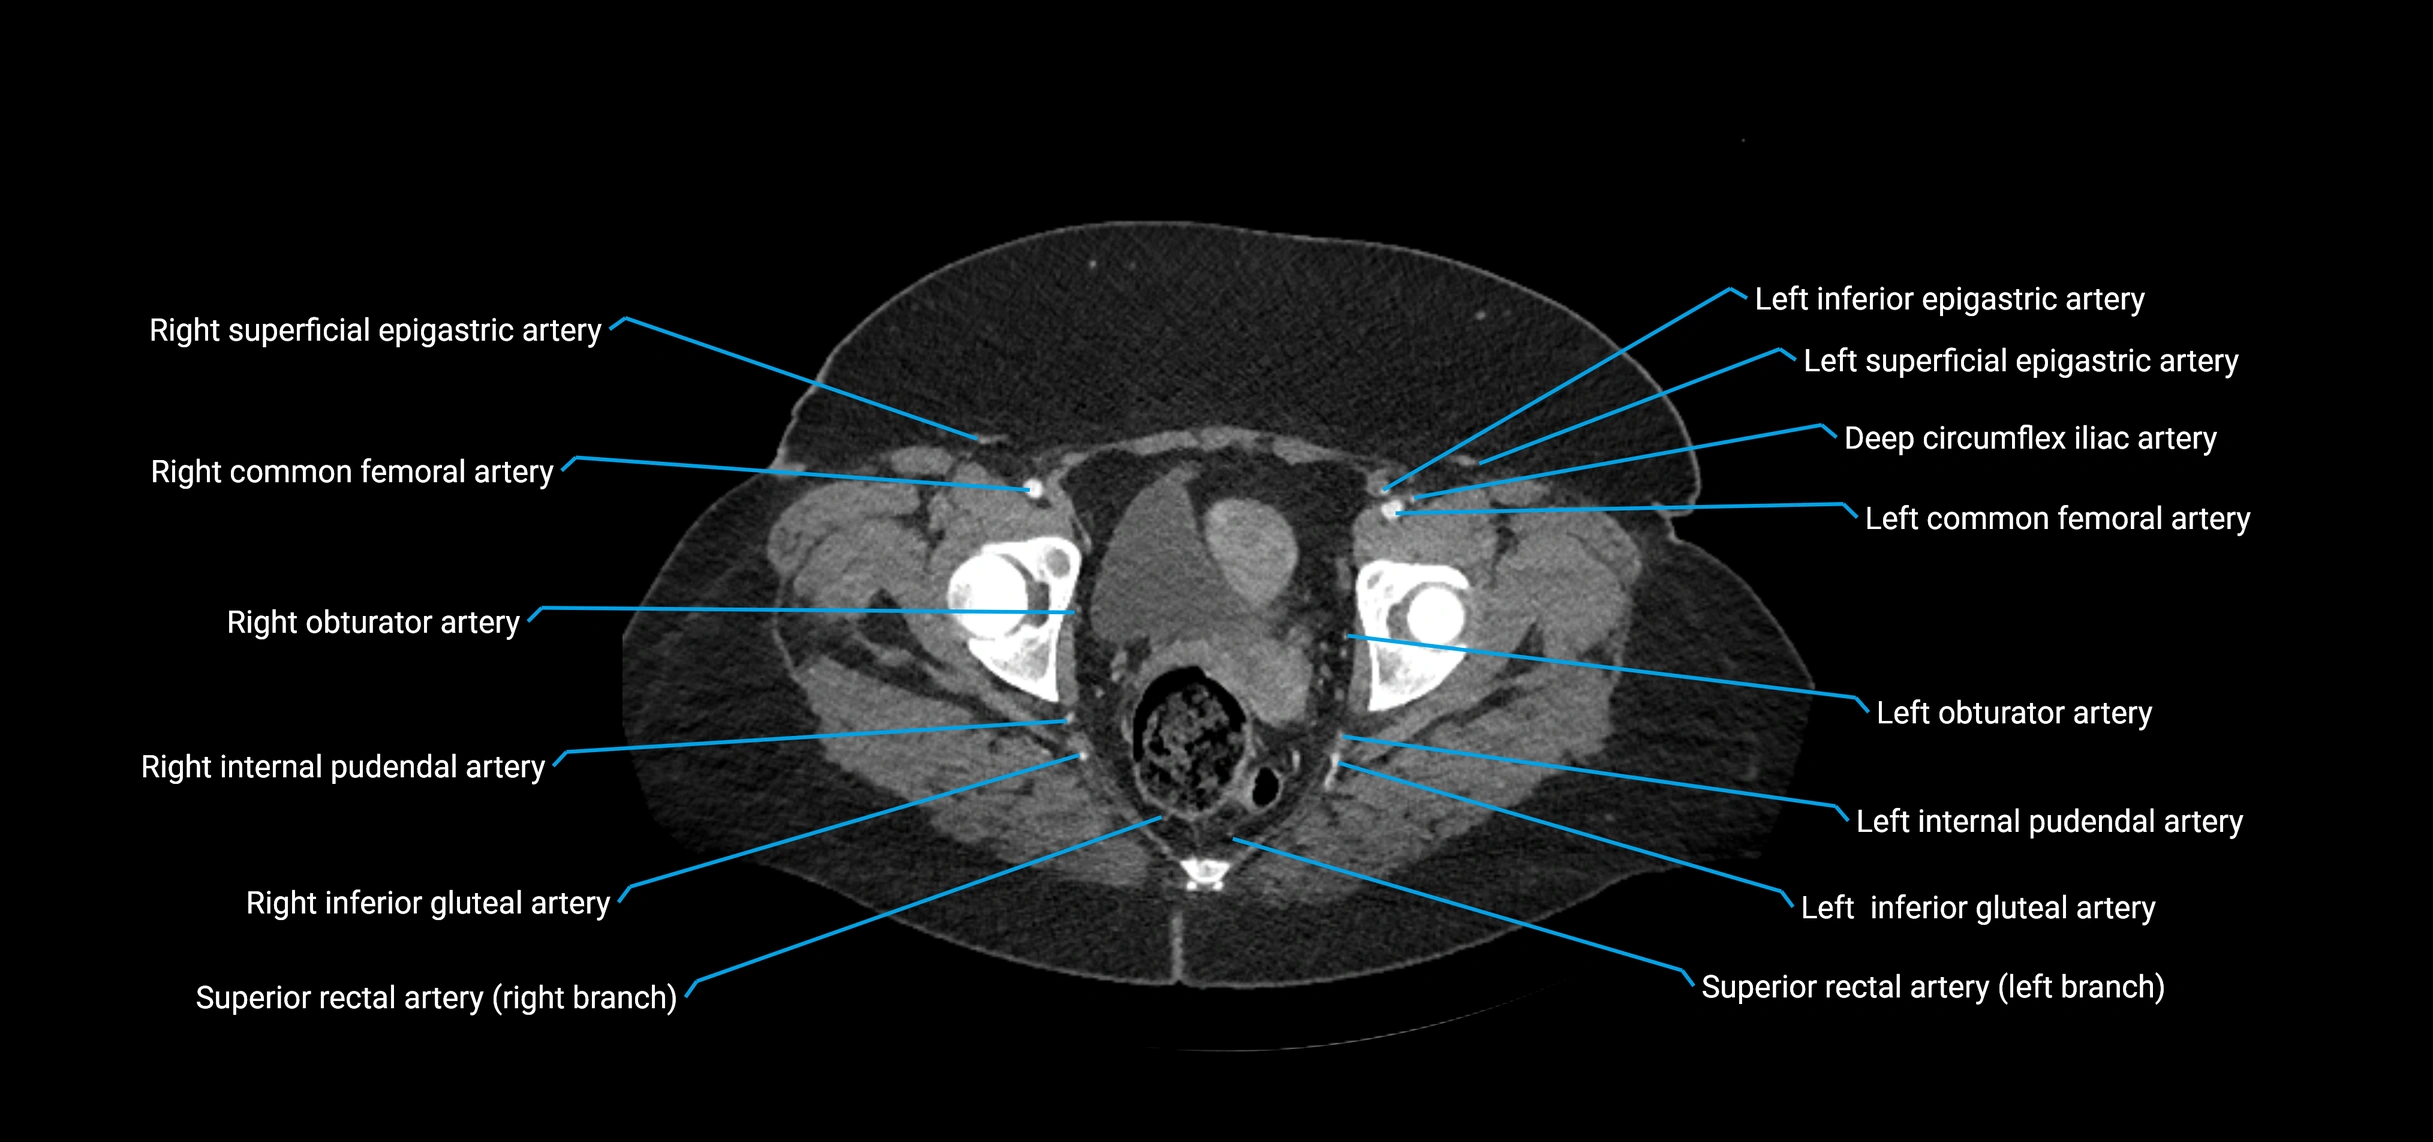

Contrast-enhanced CT (CTA):

• Gold standard for abdominal aortic imaging

• Provides excellent detail of lumen, wall, aneurysm, thrombus, and branch vessels

• Multiplanar and 3D reconstructions help in aneurysm measurement, stent graft planning, and dissection evaluation